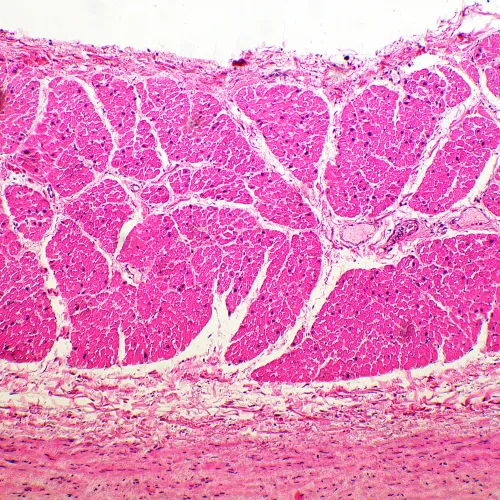

Микроскоп MAGUS Bio 260T – рутинная модель, которая оснащена интеллектуальным освещением, встроенным ЖК-экраном и может дополняться компонентами, которые расширят возможности микроскопа для работы в темном поле, с фазовым контрастом, в люминесцентном свете или с применением поляризации.

В базовой комплектации микроскоп работает в светлом поле с прозрачными и полупрозрачными тонкими биологическими препаратами. Может применяться в лабораториях и научных учреждениях для рутинных исследований, для обучения молодых специалистов.

- В базовой комплектации микроскоп предназначен для исследования биологических образцов в светлом поле в проходящем свете